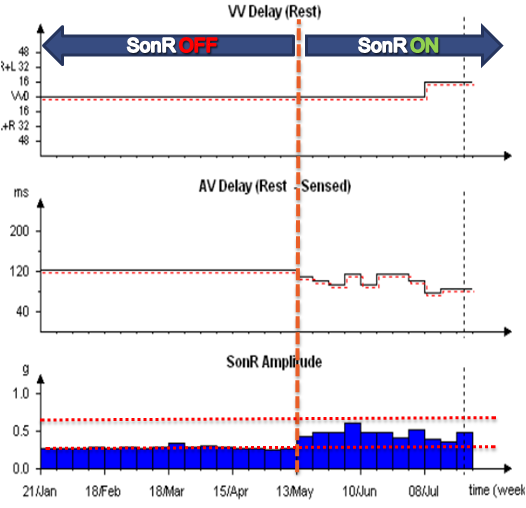

Les systèmes CRT-D SonR numérisent et analysent le signal SonR1 provenant de la sonde auriculaire. L'algorithme contenu dans ces défibrillateurs optimise automatiquement les délais AV et VV sur une base hebdomadaire.

L'optimisation du SonR, réalisée dans la nuit de dimanche à lundi, est un test hebdomadaire automatique de 69 combinaisons de délais AV/VV. Chaque combinaison de délais AV/VV est ajustée dans une séquence de 3 cycles adaptatifs suivis de 6 cycles pour mesurer le SonR.

Données mémorisées

L'amplitude moyenne du signal SonR et l'adaptation des délais AV et VV optimisés chaque semaine sont disponibles dans les mémoires du SonR CRT-D.